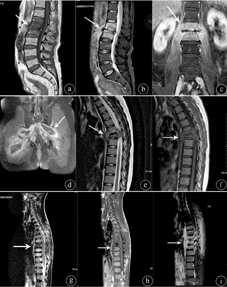

5例非结核性感染病例共累及8个椎体,包括6个腰椎,2个骶椎。其中3例于就诊时出现椎间隙明显狭窄,2例出现椎间隙轻度狭窄。4个椎体呈现边缘性骨质破坏,边界较清。6个椎体出现虫蚀状骨质破坏,主要累及椎体终板骨质,病变边界不清。受累椎体均表现为T1WI低信号(图1a),T2WI呈不均匀高信号(图1b)或高低混杂信号,压脂序列(SPAIR)呈高信号,增强扫描病变明显不均质强化(图1c),病变主要分布于终板、椎体内部,以椎体终板为中心信号向椎体内逐渐减低。双侧附件均未累及。2例伴有范围较广的脓肿形成,累及部分腰大肌、髂腰肌及臀肌,形态不规则,边缘不清,增强扫描脓肿壁呈明显厚薄不均、环形强化,脓肿内部未见强化(图1d),边缘见斑片状强化。3例病变椎体周围软组织仅表现为增厚,增强扫描轻中度片絮状强化。同时合并椎间盘炎2例,均发生在腰椎,1例T2WI及SPAIR序列均呈高信号,1例信号无明显异常。1例Langerhans组织细胞增生症,发生在T6椎体,椎体明显压缩呈楔形变、"扁平椎"改变,局部后凸畸形(图1e、图1f),病变同时累及椎体及双侧椎弓,T1WI呈等信号,T2WI呈不均匀稍高信号,椎体周围见明显软组织肿块影,亦呈稍长T1稍长T2异常信号,于矢状位和冠状位上呈"哑铃状"外观,后缘相应节段后纵韧带及软组织肿块后凸,相应椎管内硬膜囊及脊髓受压。邻近上个椎间隙似见轻度狭窄。本例未行MRI增强检查。

注:非特异性感染(a~d):a.L2、3椎体呈弥漫性信号异常,T1WI呈低信号(箭头所示);b.T2WI呈不均匀高信号(箭头所示);c.增强扫描病变明显强化(箭头所示);d.增强扫描双侧髋部、臀部广泛软组织脓肿(箭头所示);Langehans组织细胞增生症(e~f):e.T6椎体呈"扁平椎"外观,T2WI呈不均质高信号(箭头所示);f.T1WI呈稍低信号(箭头所示);毛细血管瘤(g~i):g.T6~10椎体广泛性信号异常,T2WI序列仅T8为低信号(箭头所示),余椎体呈混杂高信号;h.T1WI序列T6~8椎体呈低信号为主,旁见斑点、片状高信号影(箭头所示);i.增强扫描后椎体及相应附件呈不均匀强化(箭头所示)

1例毛细血管瘤,病变范围较广泛,累及T6-10多个椎体(图1g),胸椎以病椎为中心向右侧凸,同时累及左侧椎弓根及棘突,3个胸肋关节亦可见受累。MRI上T1WI病变呈低信号为主,部分椎体内见斑点状高信号影(图1h),T2WI压脂序列为混杂高信号,增强扫描椎体不均质中度强化,内见纵行排列的低信号影和高信号影间隔(图1i)。病椎周围见增厚的软组织影,增强扫描软组织呈不均质明显强化。

本组误诊病例中,非结核性(非特异性)感染例数最高(5/7),各种感染途径均可引起椎体和(或)椎间盘感染,尤其感染灶周围伴随着软组织肿块,随着软组织肿块内部液化坏死形成脓肿,很难与结核性脓肿鉴别。MRI表现为受累椎体T1WI低信号,T2WI高信号,椎间盘通常呈现不均匀的高信号。研究发现,在缺乏分支杆菌蛋白水解酶情况下椎间盘也可不受累而表现为正常信号[2]。同脊椎结核鉴别要点是后者病程上进展较缓慢,软组织肿块较小,或仅表现为软组织轻度的肿胀、增厚。单纯椎间盘或椎间隙炎时,早期仅表现为T2WI髓核低信号消失[3],而出现椎间隙变窄较晚,脊椎结核早期即合并椎间隙变窄。普通细菌引起化脓性感染所形成的脓肿,MRI上增强扫描脓肿壁呈环形强化,内部脓液不强化[4],Jung等[5]认为非特异感染尤其是化脓性感染形成的脓肿形态各异,范围更大,脓肿壁厚薄不均,而结核性冷脓肿边界清晰,脓肿壁薄且光滑,增强后强化均匀,因此脓肿特点是两个疾病主要鉴别征象。本组其中一例(图1d)由金黄色葡萄球菌引起的化脓性感染病例,MRI表现为下腰椎椎体边缘性破坏伴有周围巨大软组织肿块,软组织肿块延伸至盆腔形成范围广泛且形态不规则脓肿,脓肿壁厚薄不均,增厚扫描明显强化,脓液不强化。本组含有一例白色念珠菌引起真菌椎体感染,由于MRI表现同非特异感染未见明显区别,未分别论述。

毛细血管瘤是发生于椎体血管瘤的一个少见亚型,病理学表现为大量增生的毛细血管及扩张的血窦,经常发生于神经外科术后[6],T1WI及T2WI上的低信号,为粗大的骨小梁[7],伴随着低信号旁小斑片状高信号为脂肪组织,增强扫描病变强化(图1g,图1h,图1i)。结合CT上出现"灯芯绒征"及"栅栏征"[8]等相对特异性征象,较易做出正确诊断。该病一般不引起椎间隙变窄。仔细辨别本误诊病例基本具备血管瘤特征性改变即:椎体形态保持完整,椎体未见虫蚀性、边缘性骨质破坏,椎体内见纵行低信号影及伴随周围的纵行、斑点样高信号影,同时病变范围较广泛,累及T6-10椎体及附件,椎间隙狭窄不明显,仅表现为部分椎间盘信号异常。